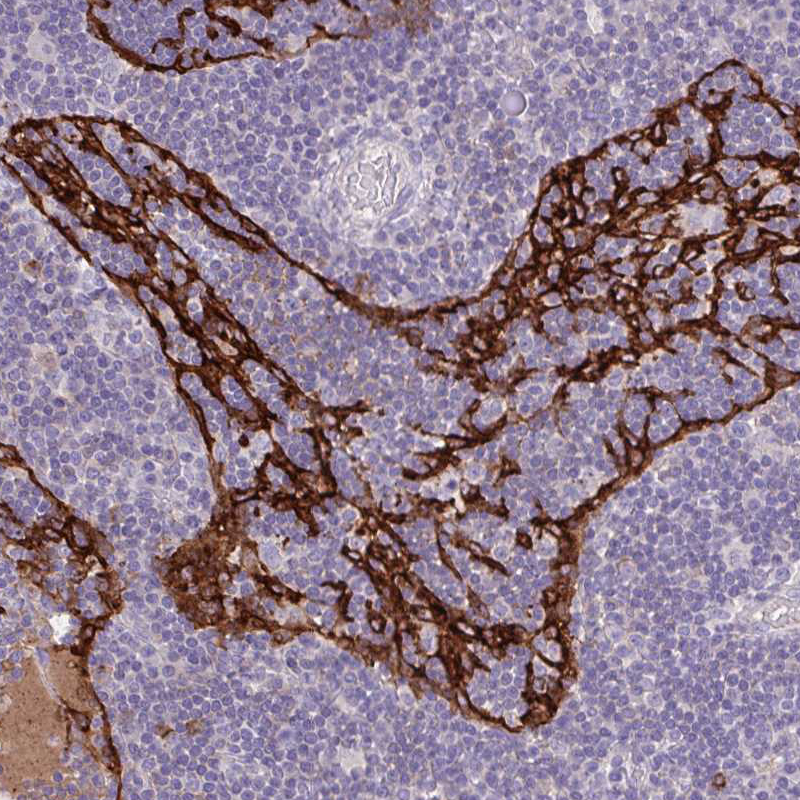

Immunohistochemistry analysis in human lung and pancreas tissues using HPA063793 antibody. Corresponding MARCO RNA-seq data are presented for the same tissues.